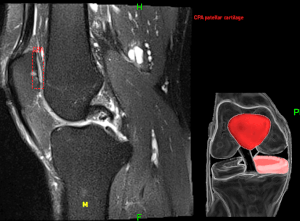

Currently our easily integrable software enables the fully automatic, prompt & robust annotation of the relevant anatomic details and detection of the most frequent knee lesions: ACL & meniscal tears, articular cartilage lesions, patellar instability measurments, Baker cysts.